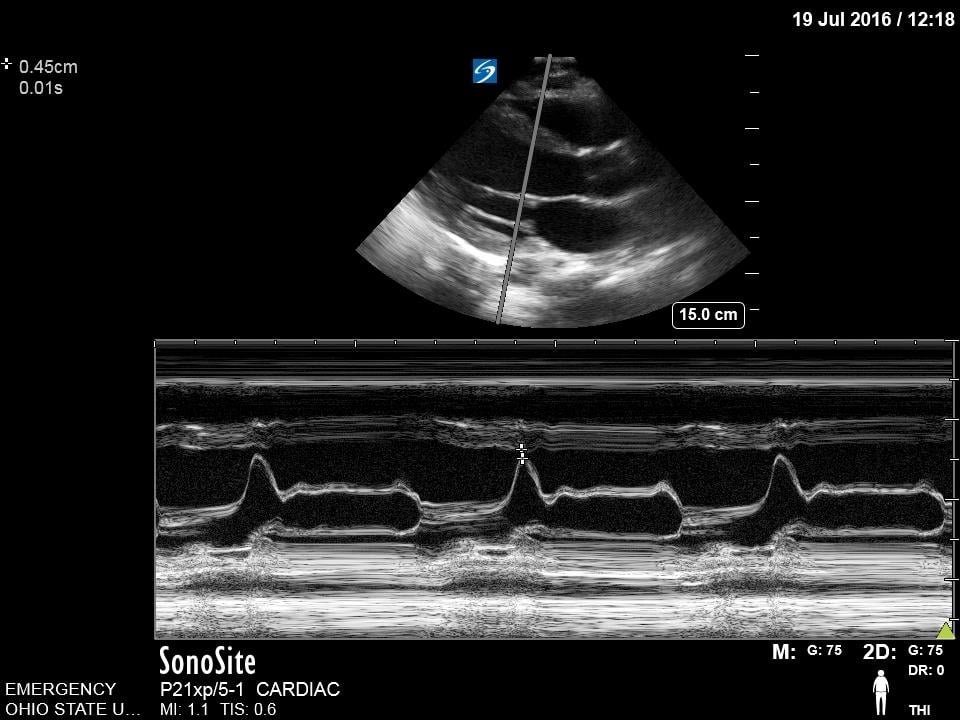

E-point Septal Separation

This is a technique that is commonly employed to provide an objective measurement of systolic function of the left ventricle. Using M-mode, capture the distance between the anterior leaflet of the mitral valve and the interventricular septum. A measure >7mm correlates with reduced cardiac function.13 This measurement may not be accurate in cases of aortic regurgitation, mitral stenosis, hypertrophic cardiomyopathy, and non-sinus rhythm.

Figure 11. Normal E-point septal separation